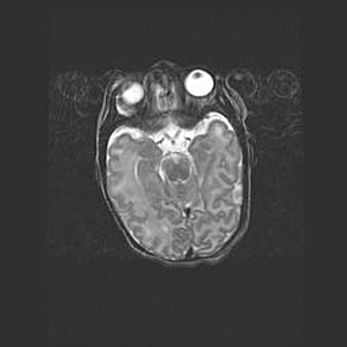

Множественные кисты обоих полушарий головного мозга, наибольшая из них в правой затылочной области. Ассиметричная атрофическая гидроцефалия.

Возраст: 7 месяцев

Вес: 5660 г

Пол: мужской

Окружность головы: 41,5 см

Срок гестации: 28-29 недель

Кисты головного мозга развиваются в результате многоочаговых некрозов вещества мозга и возникают вследствие перенесенной перинатальной инфекции, менингитов, энцефалитов, асфиксии, родовой травмы, расстройств мозгового кровообращения различного генеза. Образованию кист в веществе головного мозга плодов и новорожденных способствуют такие факторы, как высокое содержание в нем воды, недостаточная (или отсутствие) миелинизация и слабая астроглиальная реакция на повреждение.

Кисты могут сочетаться с гидроцефалией и другими поражениями головного мозга.